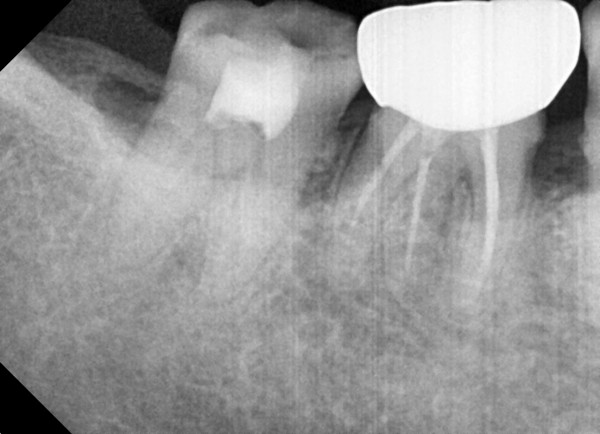

충치치료&신경치료 하루에 끝나는 신경치료